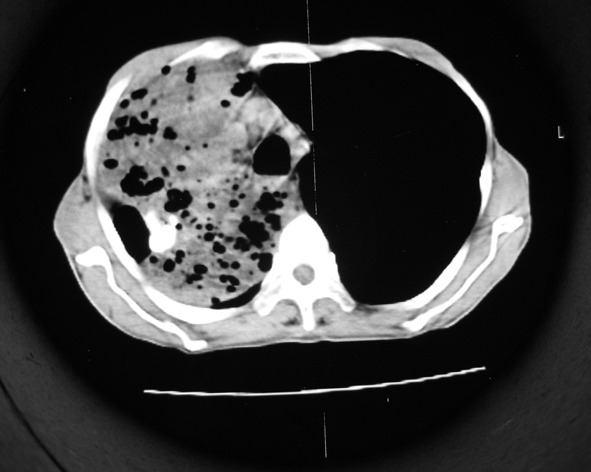

男53岁,咳嗽气短,以往身体健康.

右肺上叶多发多形态空洞及增殖灶,可见团块钙化,胸膜肥厚、粘连,考虑继发型肺结核可能性大

1.右肺上叶干酪性肺炎,2。肺气肿,肺大泡

右肺上中叶结核干酪性肺炎

右肺中上叶干酪性肺炎。

支持右上肺继发性肺结核并干酪性肺炎,右肺大泡,左肺代偿性气肿。